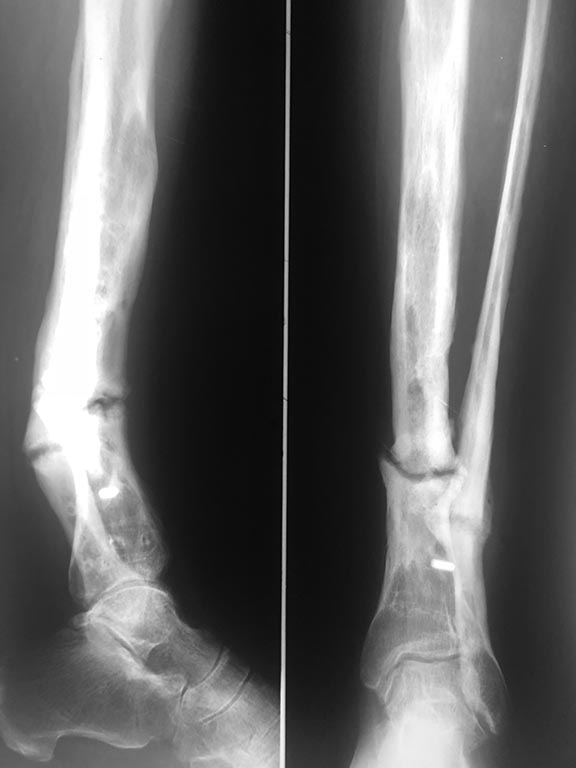

Добрый вечер! Обратилась пациентка с тугоподвижным ложным суставом

костей правой голени в

н/3 с антекурвационной деформацией и укорочением. Кратко по анамнезу- в

2011г. закрытый

перелом костей правой голени,выполнен накостный МОС, осложнение

-нагноение в раннем п/о

периоде, Удаление м/к и ЧКДО аппаратом Илизарова. Далее -резекция

большеберцовый кости в

процессе секвестрнекрэтомии,перемонтаж АВФ с попыткой билокального

ЧКДО,далее , уже в

2014г. - открытое вмешательство- костная пластика и накостный МОС, через

1 год закончилось

удалением м/к по поводу рецидивирующих свищей. В настоящее время тугой

ложный сустав ,

деформация с укорочением 3-4см.; свищей в течение 2.5 лет не было.